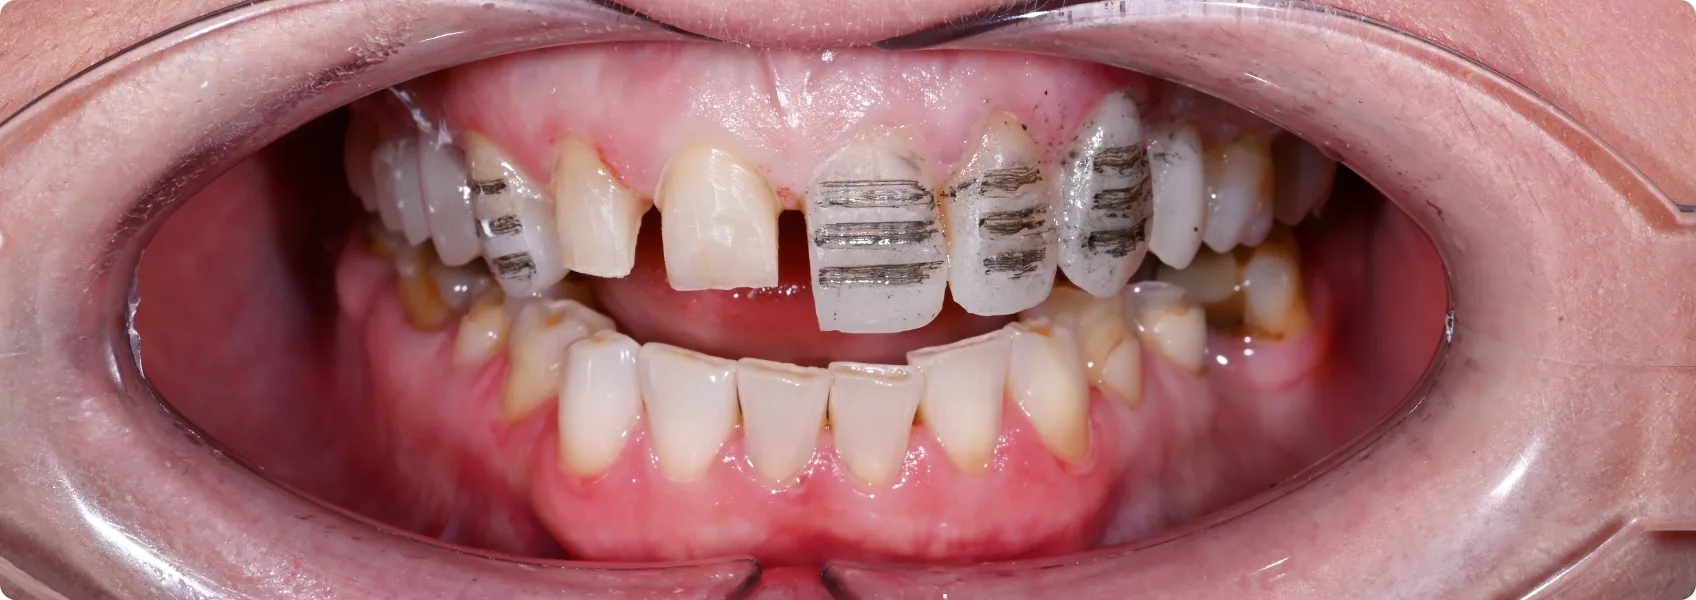

Wstępna diagnoza wykazała mocno starte, dysfunkcyjne zęby.

Dotychczasowe ustawienie zębów nie spełniało swojej funkcji. Pacjentka przez lata ścierała ich końcówki o siebie. Na powierzchni zębów pojawiały się pęknięcia i ubytki.

Pacjentka skarżyła się na obszerną nadwrażliwość.

Kiedy szkliwo — twarda, zewnętrzna warstwa ochronna zębów — ściera się, odsłania się zębina, czyli warstwa zęba ukryta pod szkliwem. W zębinie znajdują się tysiące mikroskopijnych kanalików, które prowadzą aż do nerwu zęba.

Gdy zimno, ciepło, słodkie lub kwaśne dostanie się do tych kanalików – nagły impuls bólowy trafia wprost do nerwu. To właśnie nadwrażliwość – szybka, ostra i bolesna reakcja na bodźce.